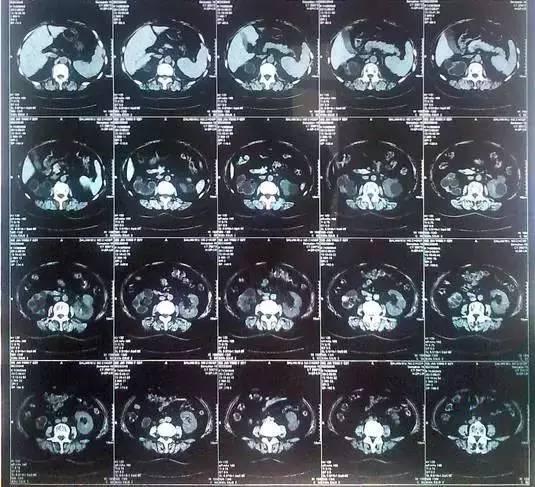

55歲的老何是金華東陽(yáng)市橫店鎮(zhèn)人,一名普通工人。因?yàn)轭l繁腰疼去醫(yī)院檢查,結(jié)果CT顯示,他的左腎里竟然密密麻麻布滿了石頭,幾乎把整個(gè)腎都塞滿了,手術(shù)從左腎取出了420顆結(jié)石!

醫(yī)生看了CT的結(jié)果顯示,非常嚴(yán)肅的告訴他,他的左腎已經(jīng)被結(jié)石占滿,必須馬上手術(shù)治療。這次手術(shù)讓主刀醫(yī)生觸目驚心,他們居然從老何的左腎取出了420顆結(jié)石。這是他們手術(shù)生涯上從來(lái)沒有遇到過的病例。